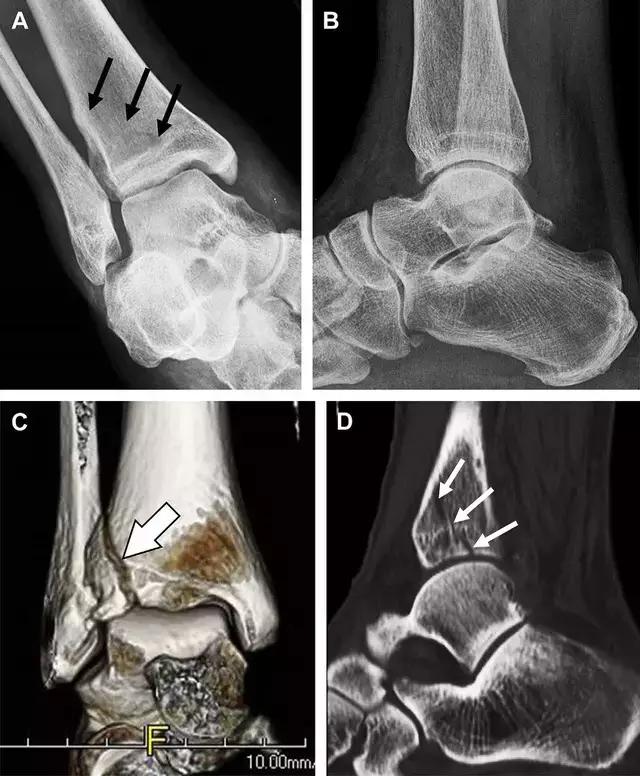

16 胫骨后踝骨折

涉及到三角韧带和外侧副韧带(LCL)的复杂性骨折常常不难发现,尤其是存在表面软组织肿胀时。然而,后胫腓韧带牵拉引起的胫骨后踝骨折则很难发现。这些骨折大小不一(图 2),却很重要,因为他们常与胫骨远端螺旋骨折有关,或者是三踝骨折的一部分。

图 2 胫骨后踝骨折。A 侧位片示来源于胫骨后踝的一个小骨折碎片(箭头),因踝部扭伤导致;B 另一位跖屈损伤的患者,侧位片示一个大骨折块(箭头)

17 胫骨结节骨折

Tillaux 骨折,是足外旋外展时,胫腓前韧带牵拉引起的一种胫骨结节撕脱性骨折。斜位片上可见典型表现(图 3)。

图 3 摔倒后胫骨结节骨折。A 正位片示一细小斜型骨折线(箭头);B 侧位片示正常;C 冠状位 CT 三维成像更清晰地显示了骨折线和骨折块大小(空箭头);D 矢状位 CT 多维重建图像示骨折位置(箭头)

18 距骨外侧突骨折

距骨外侧突骨折常因踝外翻背屈时,跟骨上外侧面撞击距骨外侧突下缘导致,或偶尔由踝内翻引起,被称为「滑雪板者骨折」。这种骨折只能在踝关节正位片上发现,而且外踝远端表面软组织肿胀往往是一个重要线索(图 4)。

图 4 距骨外侧突骨折。A 正位片示内翻损伤所致的距骨外侧突撕脱性骨折(箭头);B 另一位患者,踝外翻损伤导致典型的「滑雪板者骨折」,X 片上可见一较大的三角形骨折块(方框);C 第二位患者的 MRI 矢状位 T1 加权像示横行骨折(箭头)

19 距骨后突骨折

距骨后突有内侧结节和外侧结节,距骨后突内侧结节撕脱性骨折常发生在背屈内旋的*力暴**作用下。严重跖屈时,胫骨后缘和跟骨挤压距骨后突外侧结节呈楔形,易发生粉碎性骨折。这些骨折细微且需与三角骨鉴别。侧位片观察距骨后突骨折最佳,常规拍片很难发现,当高度怀疑这种骨折又没法做 CT 时,建议加做多个角度的外旋斜位片(图 5)。

图 5 距骨后突骨折。侧位片(A)和 MRI 矢状位 T1 加权像(B)均示后外侧突的简单骨折(箭头),再次阅片时才发现 X 线片上的骨折;侧位片(C)和 CT 横断面图像示后内侧突的粉碎型骨折(箭头)